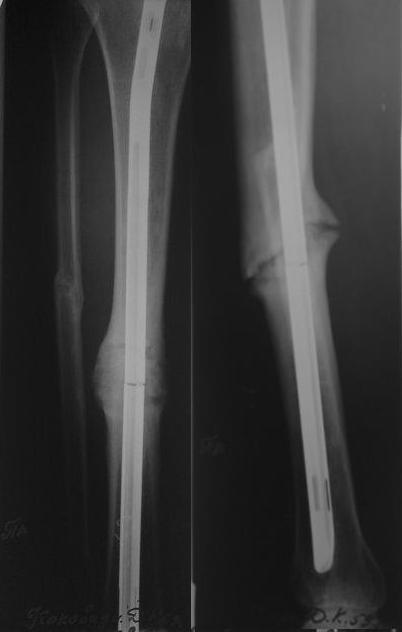

[Ortho] Ложный сустав голени

Уважаемые коллеги! У пациента 50-ти лет ложный сустав голени, перелом интрамедуллярного

штифта. Перелому около 2 лет, ходить с полной нагрузкой начал через 3 мес. после операции.

Боли при ходьбе почувствовал около 2 мес. назад.

На данный момент ходит с полной нагрузкой без посторонней опоры.

Среди коллег развернулась дискуссия по поводу способа оперативного лечения:

-удаление штифта с перештивтовыванием блокированным штифтом с рассверливанием и

остеотомией м\б кости

-стабилизация зоны ложного сустава по медиальной поверхности LCP-пластиной с декортикацией или без

-удаление штифта или без и синтез в АВФ с декортикацией или без и остеотомией м\б кости

Какой из вариантов лучше, коллеги? Еше какие варианты возможны?

Есть у кого-нибудь опыт закрытого удаления поломанного штифта с учетом наличия

ЭОП-а? Заранее благодарен за ваше мнение!